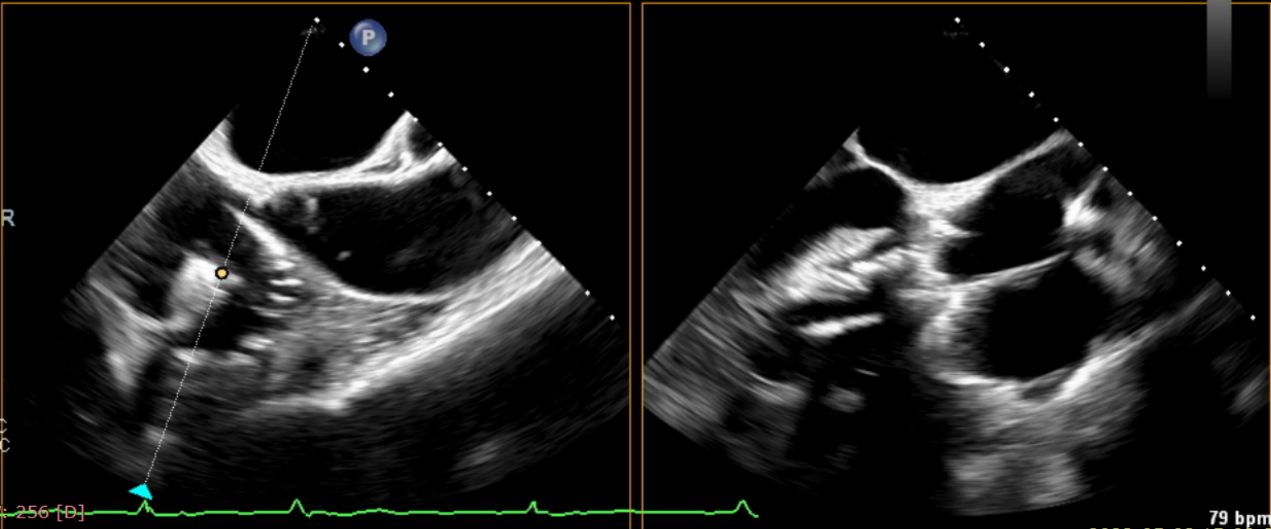

術(shù)后超聲提示無瓣周漏

術(shù)后超聲提示僅殘余輕微瓣周漏